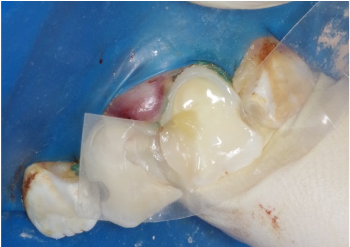

Figure 1: Shows rampant caries

Naomi was 10-years-old and suffered from acute dental phobia and rampant caries (Figure 1). She was so difficult to manage that she had not been able to receive treatment elsewhere. She was referred to me, which was not particularly convenient for her mother, who had to make the 40-mile drive to my office in Miami.

It is often best to sedate the patient in situations such as this. Having successfully managed her fear and anxiety, Naomi was cooperative, and I administered IV sedation. Figures 2 and 3 show her upper anterior teeth after removal of caries and areas of severe decalcification. Note the pulpal exposures on both central incisors.